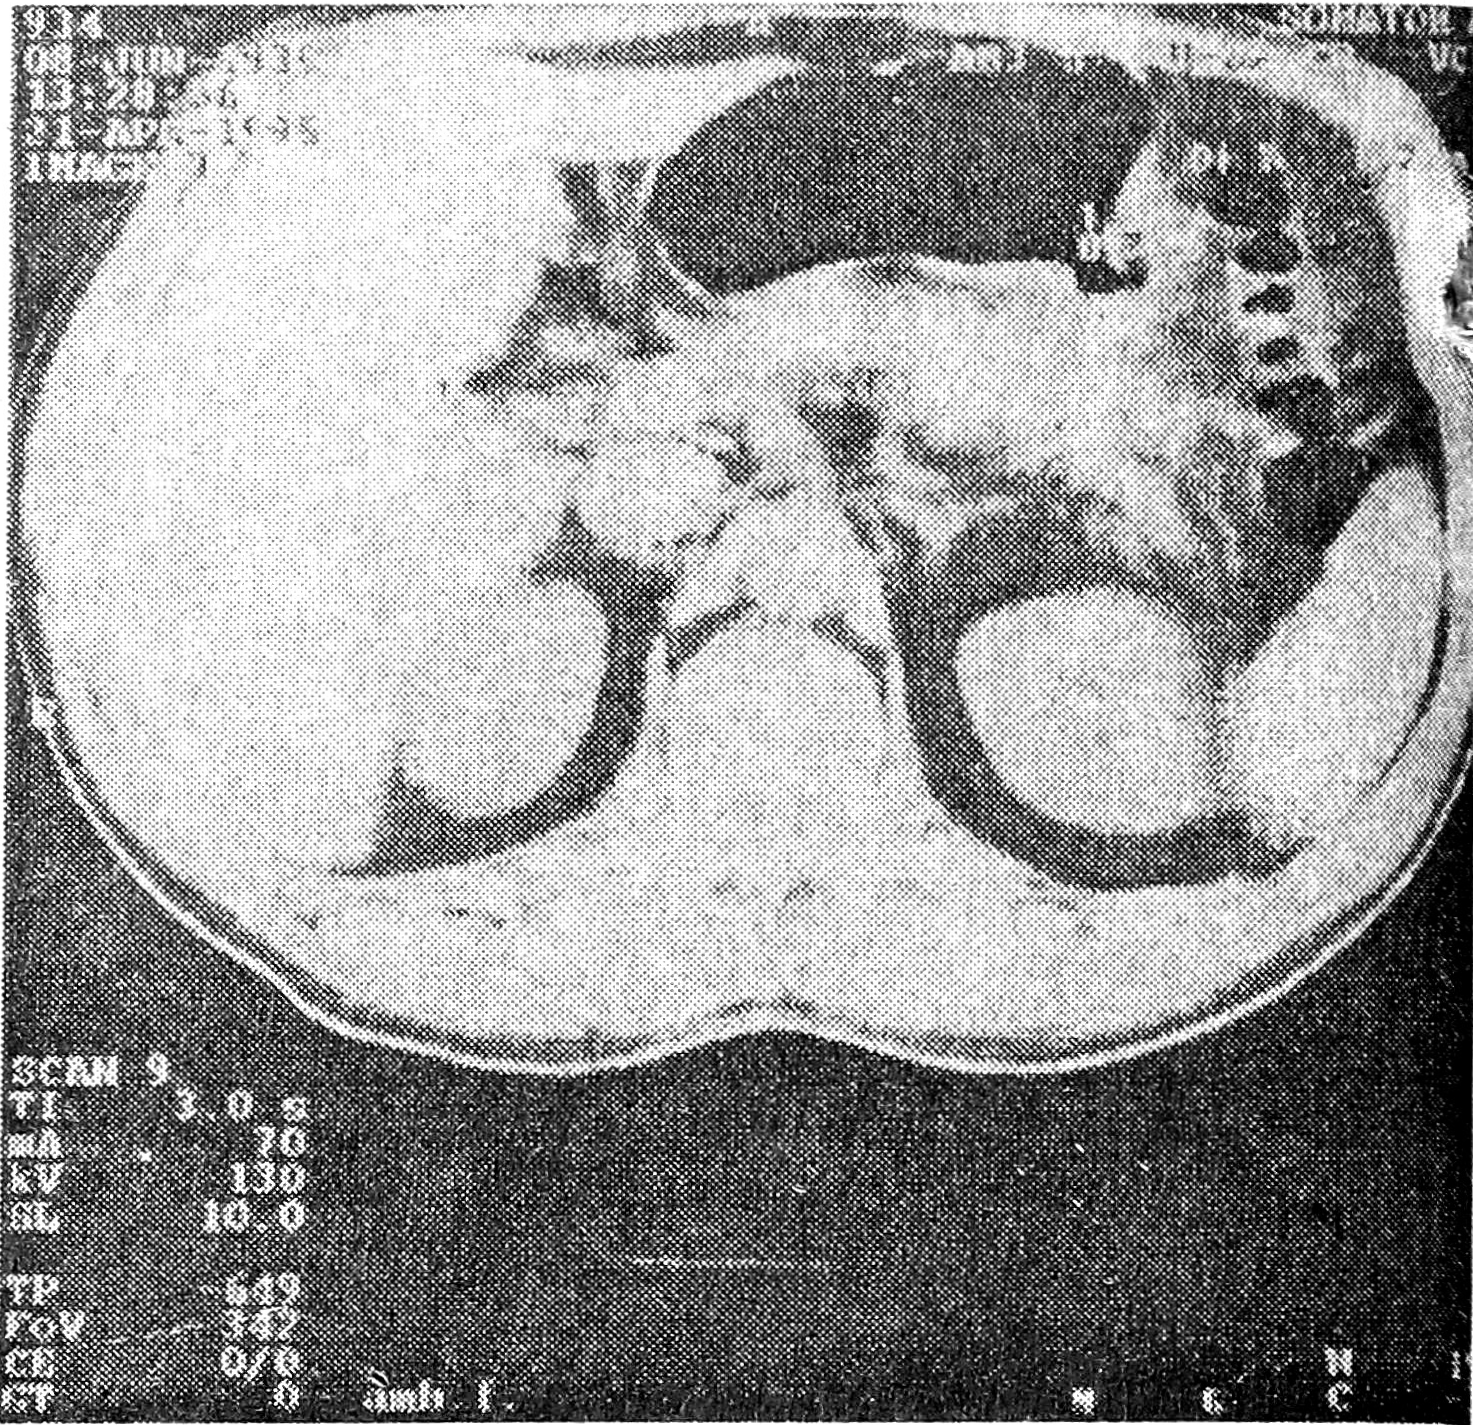

Благодаря анализу результатов компьютерно-томографических исследований желудка, нам удалось выделить основные дифференциально-диагностические признаки злокачественных и доброкачественных язв желудка. О злокачественном характере изъязвлений желудка судили по утолщению стенки желудка до 1,0 см и более на довольно большом протяжении, не соответствующему размерам язвенного дефекта. Язвенный кратер имел при этом вид плоского изъязвления с неровным, изломанным внутренним контуром, не выходящим за пределы стенки желудка; между этим утолщением и непораженной стенкой границы были нечеткими (рис.1).

Рис. 1. КТ желудка после введения воздуха больной Ф., 68 лет, со злокачественным изъязвлением. Определяется локальное утолщение стенки желудка в субкардиальном отделе до 1,1 см; язвенный кратер не выходит за пределы стенки желудка.